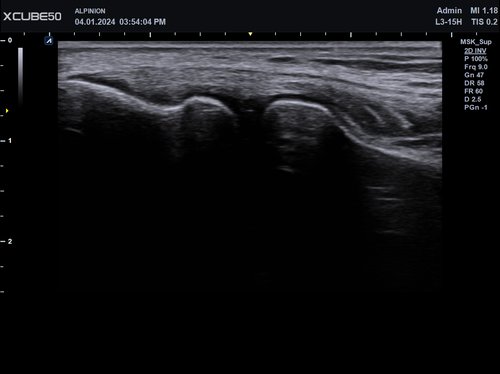

• L3-15H (3-15 MHz) für Ultraschalluntersuchungen in den Bereichen Gefäße, Weichteile, Bewegungsapparat (MSK)

Mit dem X-CUBE 50 erweitert ALPINION seine X-CUBE Serie an hochmodernen Ultraschallgeräten. Das X-CUBE 50 bietet mithilfe der X + Architecture und einem besonders abgestimmten Sondenportfolio, zu dem auch Single Crystal Schallköpfe unserer High-End Systeme gehören, eine extrem wirtschaftliche Ultraschalllösung mit beeindruckender Bildqualität.

Dieses intelligente Ultraschallsystem, das auf automatisierten Tools und einem verbesserten Workflow basiert, ermöglicht den Verzicht häufiger Anpassungen durch den Arzt und erhöht so die Genauigkeit und Effizienz bei der Diagnostik. Mit seiner kompakten Bauweise ist das X-CUBE 50 auch in kleinen Behandlungszimmern einsetzbar.